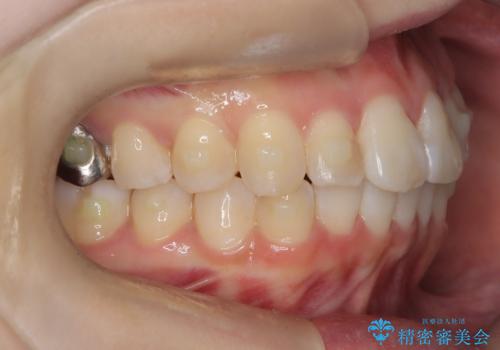

前歯のガタつきをマウスピース矯正で改善

- 前歯のガタツキが気になると来院されました。

奥歯の噛み合わせは綺麗に噛んでいたため、前歯の叢生(でこぼこ)に集中して治療するように計画しました。